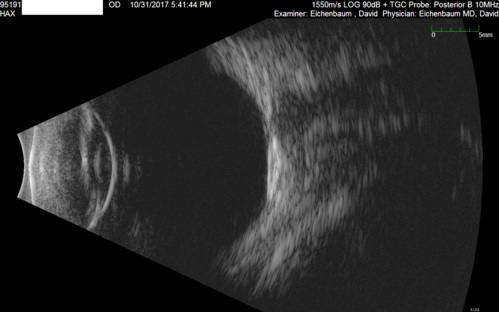

Choroidal Osteoma - 13 year old - Good Vision 20-40 - B-scan Ultrasound